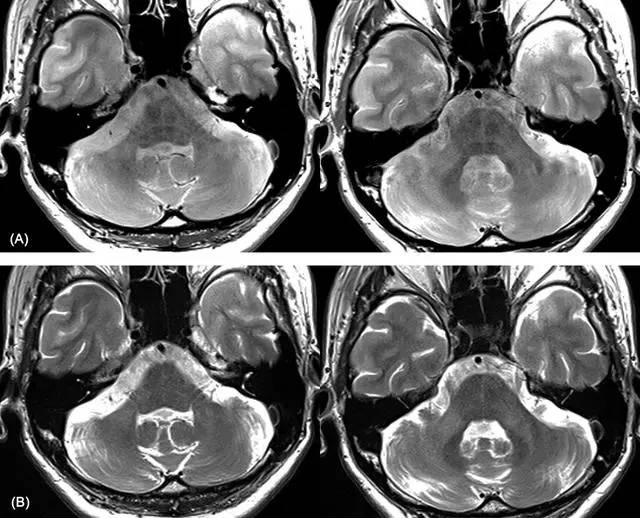

下部,常位于前联合两侧);上图示:(a)pdwi示双侧前穿质高信号区域(箭)